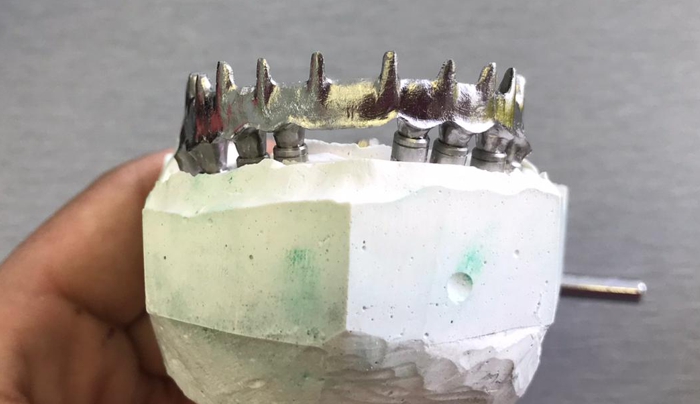

Ukázky naší práce

Celkové hybridní náhrady s otvory pro upevnění v dutině ústní pomocí dentálních implantátů